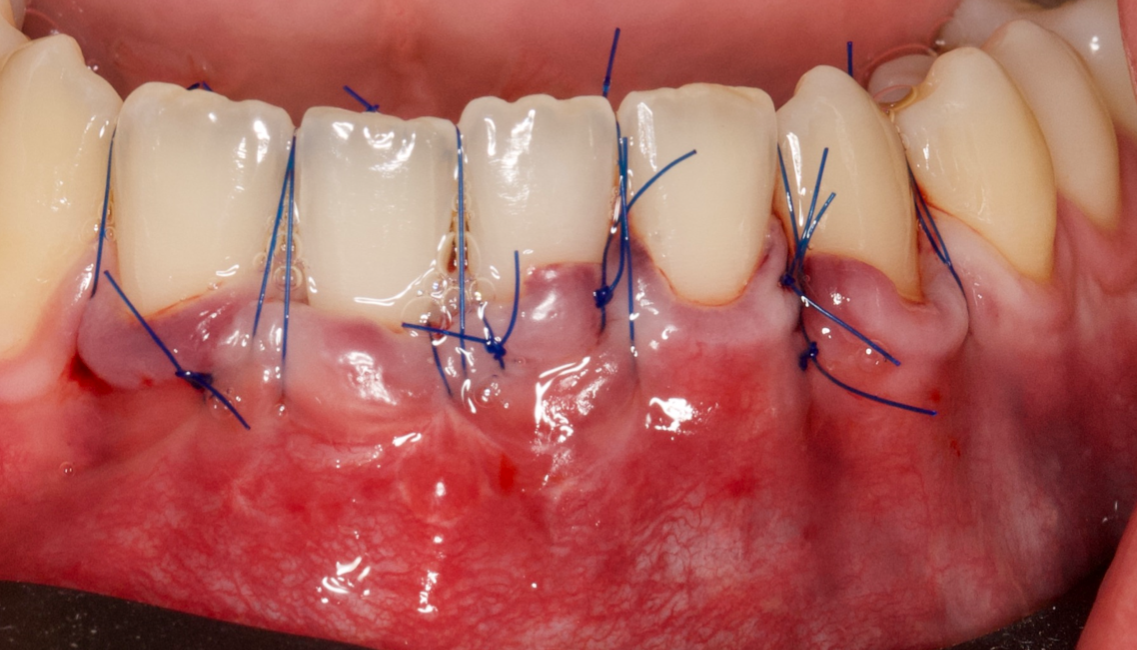

Os enseñamos este nuevo caso el Dr. Arturo Sánchez Colodro en nuestra clínica dental de Jaén, nos muestra un caso donde se puede apreciar con mucha claridad el antes y después de un caso de recesiones inferiores. Este caso ha sido tratado con la última y más avanzada tecnología en digitalización dental.

Fotografías del proceso: